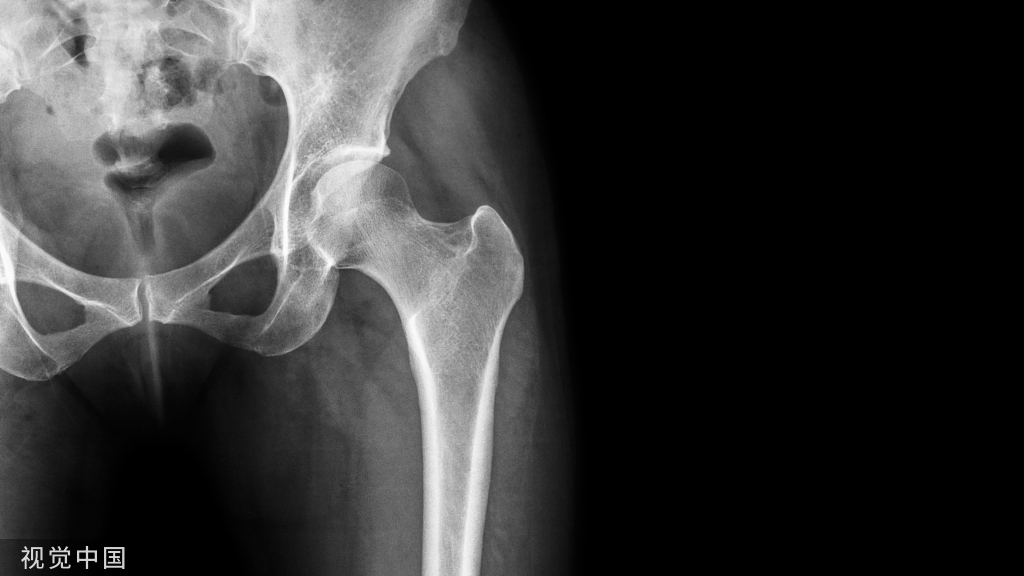

膝关节的解剖

膝关节:结构最复杂、损伤最多的关节组成:内、外侧胫股关节和髌股关节包括:骨、半月板、韧带、肌腱、软骨、滑膜等结构